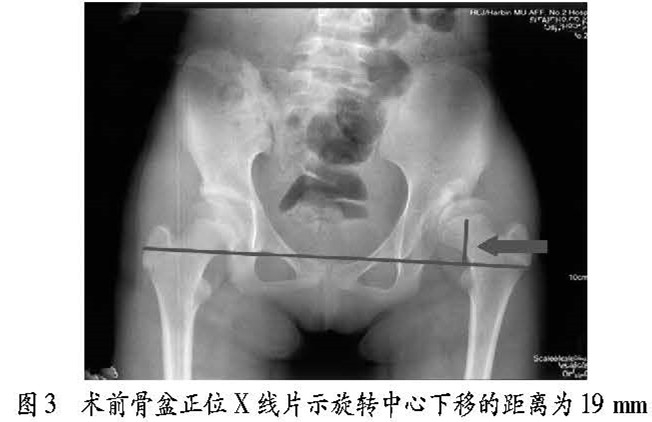

b)30 岁女性患者, 左侧髋曰发育不良, 左侧髋关节疼痛 , 行走时疼痛症状 3年, 跛行, Harris 评分为 70 分,行左侧髋臼旋转截骨术。术后旋转中心由术前的 19 mm 下降至 14 mm,手术前后影像学资料见图 3~ 4。